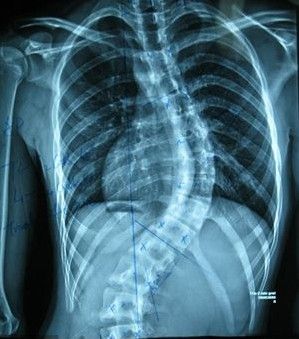

对于强直性脊柱炎,大家应该并不陌生,该病给患者的生活造成的影响是很大的,那么强直性脊柱炎的原因有什么呢?下面医生就将为大家讲述一下,希望对患者是有所帮助的。

第一、遗传因素也是常见引起强直性脊柱炎的原因,因为绝大多数强直性脊柱炎患者都会携带一种HLA-B27阳性的抗原,一般家族遗传阳性率较高,有这种抗原的人患类风湿的几率是正常人的2-10倍,强直性脊柱炎的发病率则是30倍。

第二、强直性脊柱炎的原因还有感染因素,泌尿生殖系感染也会引发该病,这是因为盆腔感染会经淋巴而散播到骶髂关节和脊柱,甚至还会引发全身症状及周围关节、肌腱和眼色素膜的病变,所以要注意感染因素。

第三、内分泌失调或代谢障碍有关,因为该病男性比较常见,所以认为与内分泌和代谢因素有关,其实内分泌与代谢出现障碍还会影响人们的身体平衡状态。这是常见的强直性脊柱炎病因。